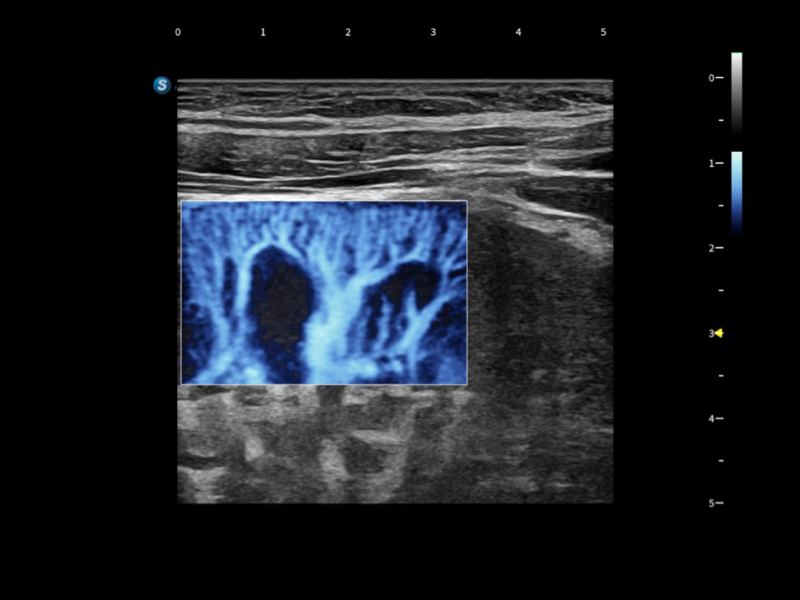

通過光照模型,使二維血流顯示出立體的效果,增加血流的敏感性、成束性,減少外溢??梢院推渌煌难骷夹g(shù)聯(lián)合使用,融合不同技術(shù)的優(yōu)勢(shì)。輕松應(yīng)對(duì)微小血管,增強(qiáng)血流的立體效果,提升視覺敏感性。

通過創(chuàng)新的Matrix E自適應(yīng)濾波算法,能有效濾除軟組織和噪聲信號(hào),最大限度保留超低速微細(xì)血流的信號(hào);結(jié)合超長(zhǎng)時(shí)間域算法,極大提升細(xì)微血流的敏感性和空間分辨率,更真實(shí)的反應(yīng)組織、包塊的血流灌注情況。